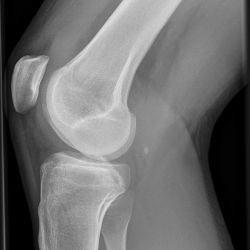

Tibiakopffraktur (nicht disloziert)